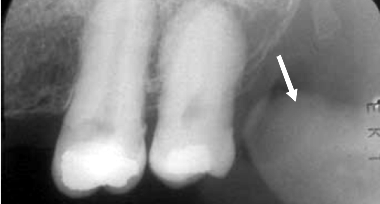

Com base na radiografia periapical acima, assinale a alternativa que apresenta a estrutura anatomorradiográfica indicada pela seta.